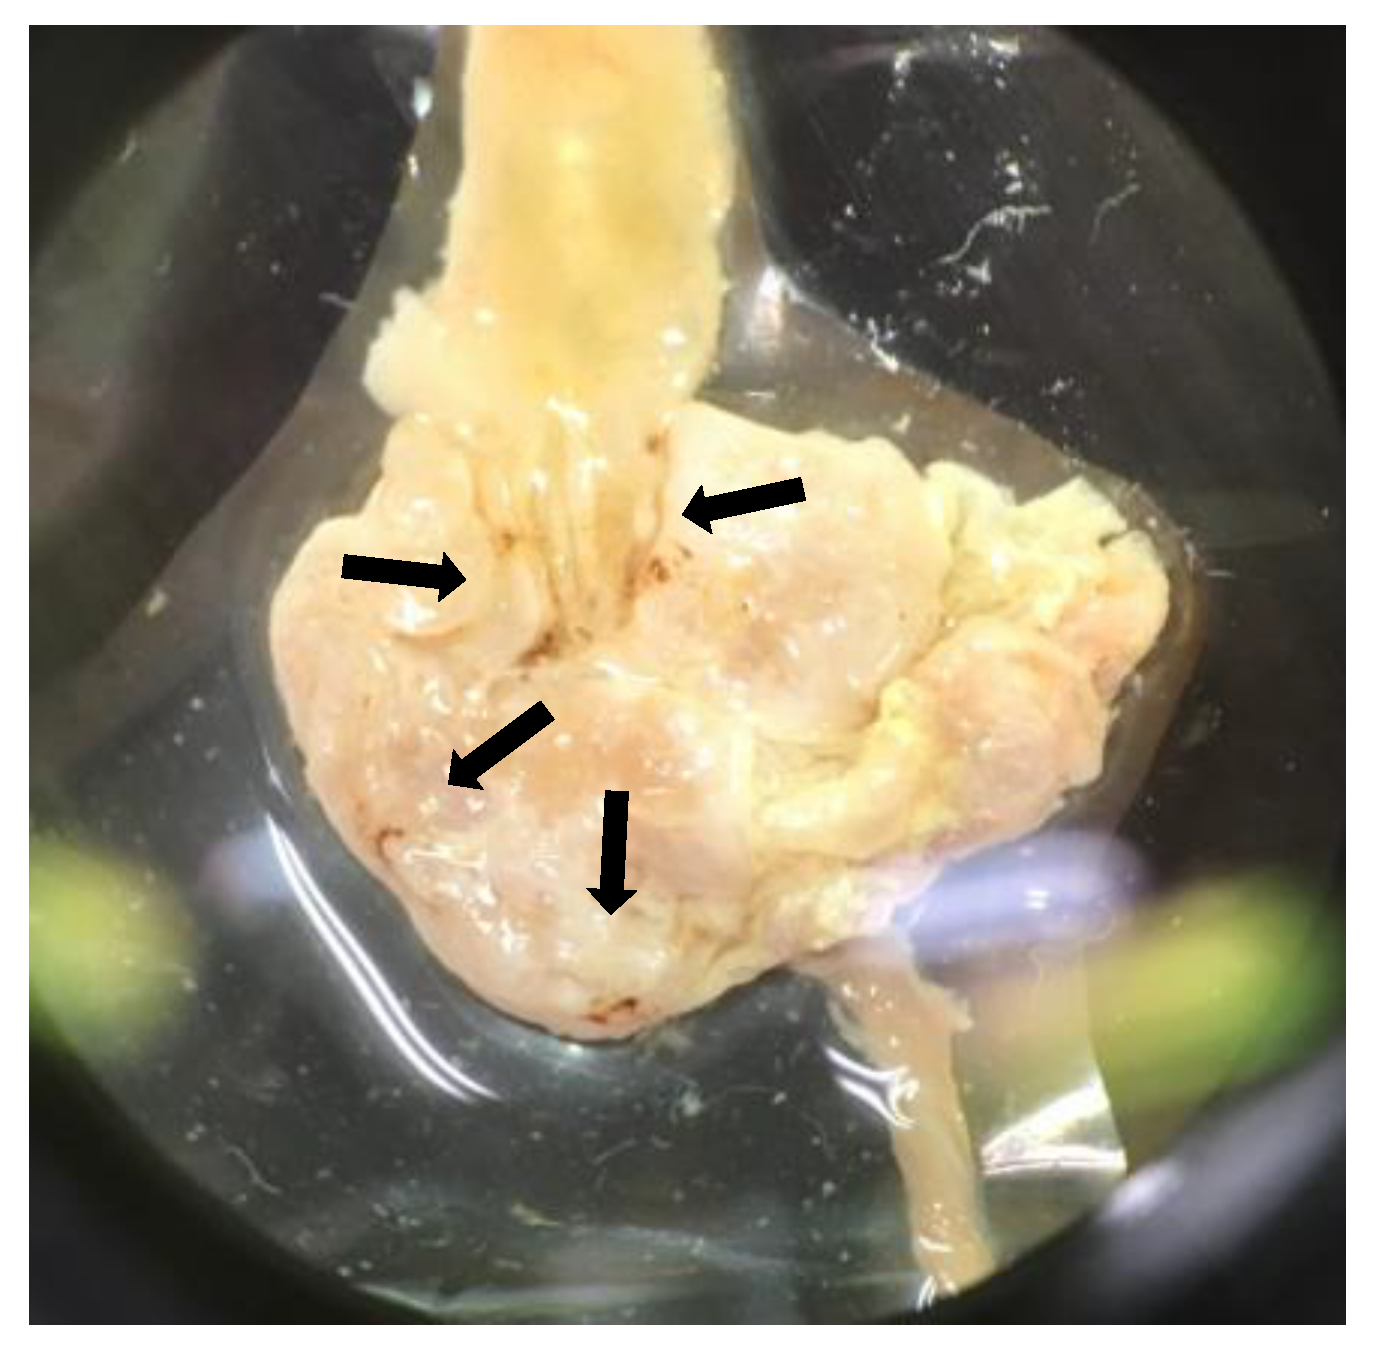

3.6. Autopsy Findings, and Histological Assessment of the Stomach and Duodenum